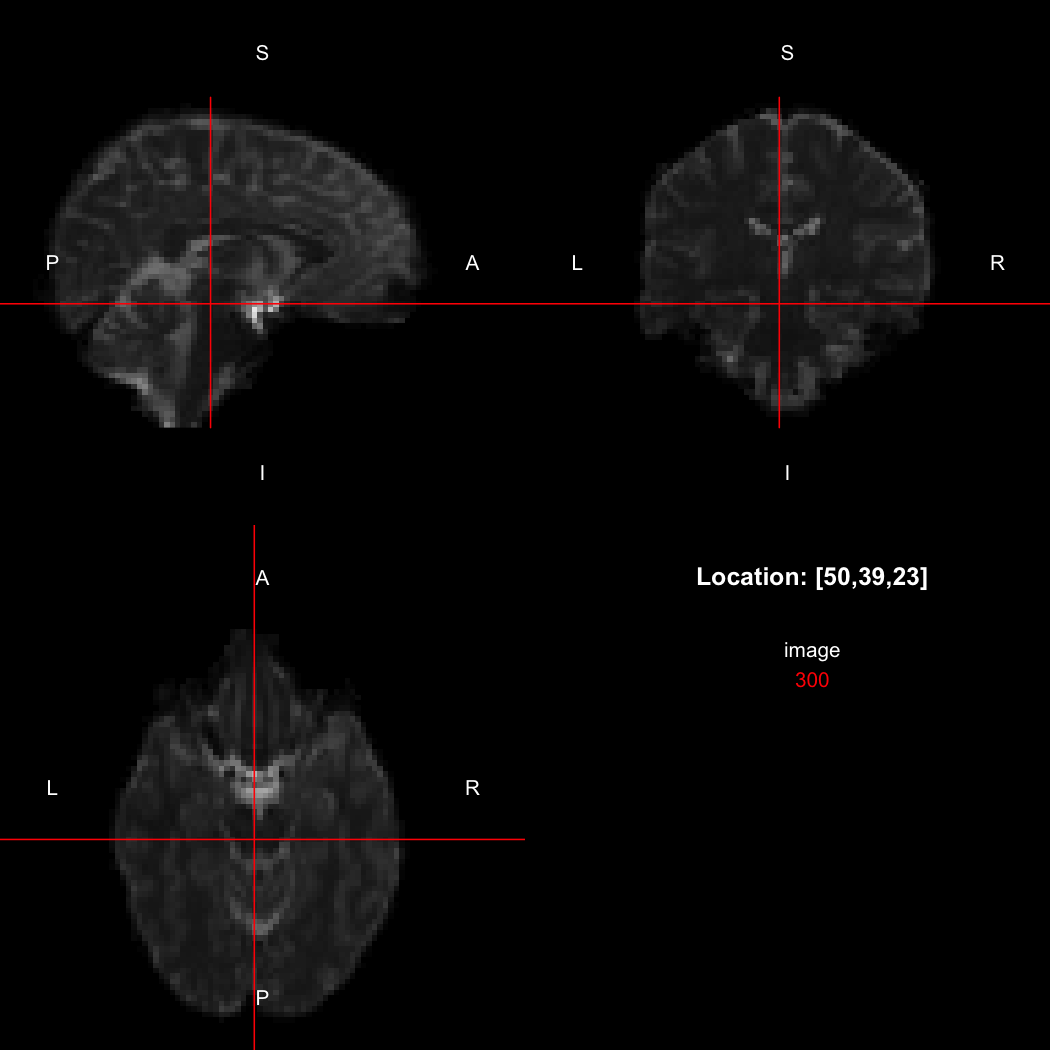

The package contains a basic image viewer, which can be used interactively or noninteractively to examine 2D or 3D images.

view(image)

By default, the viewer shows labels indicating image orientation, crosshairs pinpointing

the currently selected location, the numerical indices of the current

location, and the value of the image at that location. Options allow

each of these to be turned off, for the content of the bottom-right

panel to be customised entirely, for the colour scale to be changed, and

for additional images to be layered on top of the base image. See

?view for details.